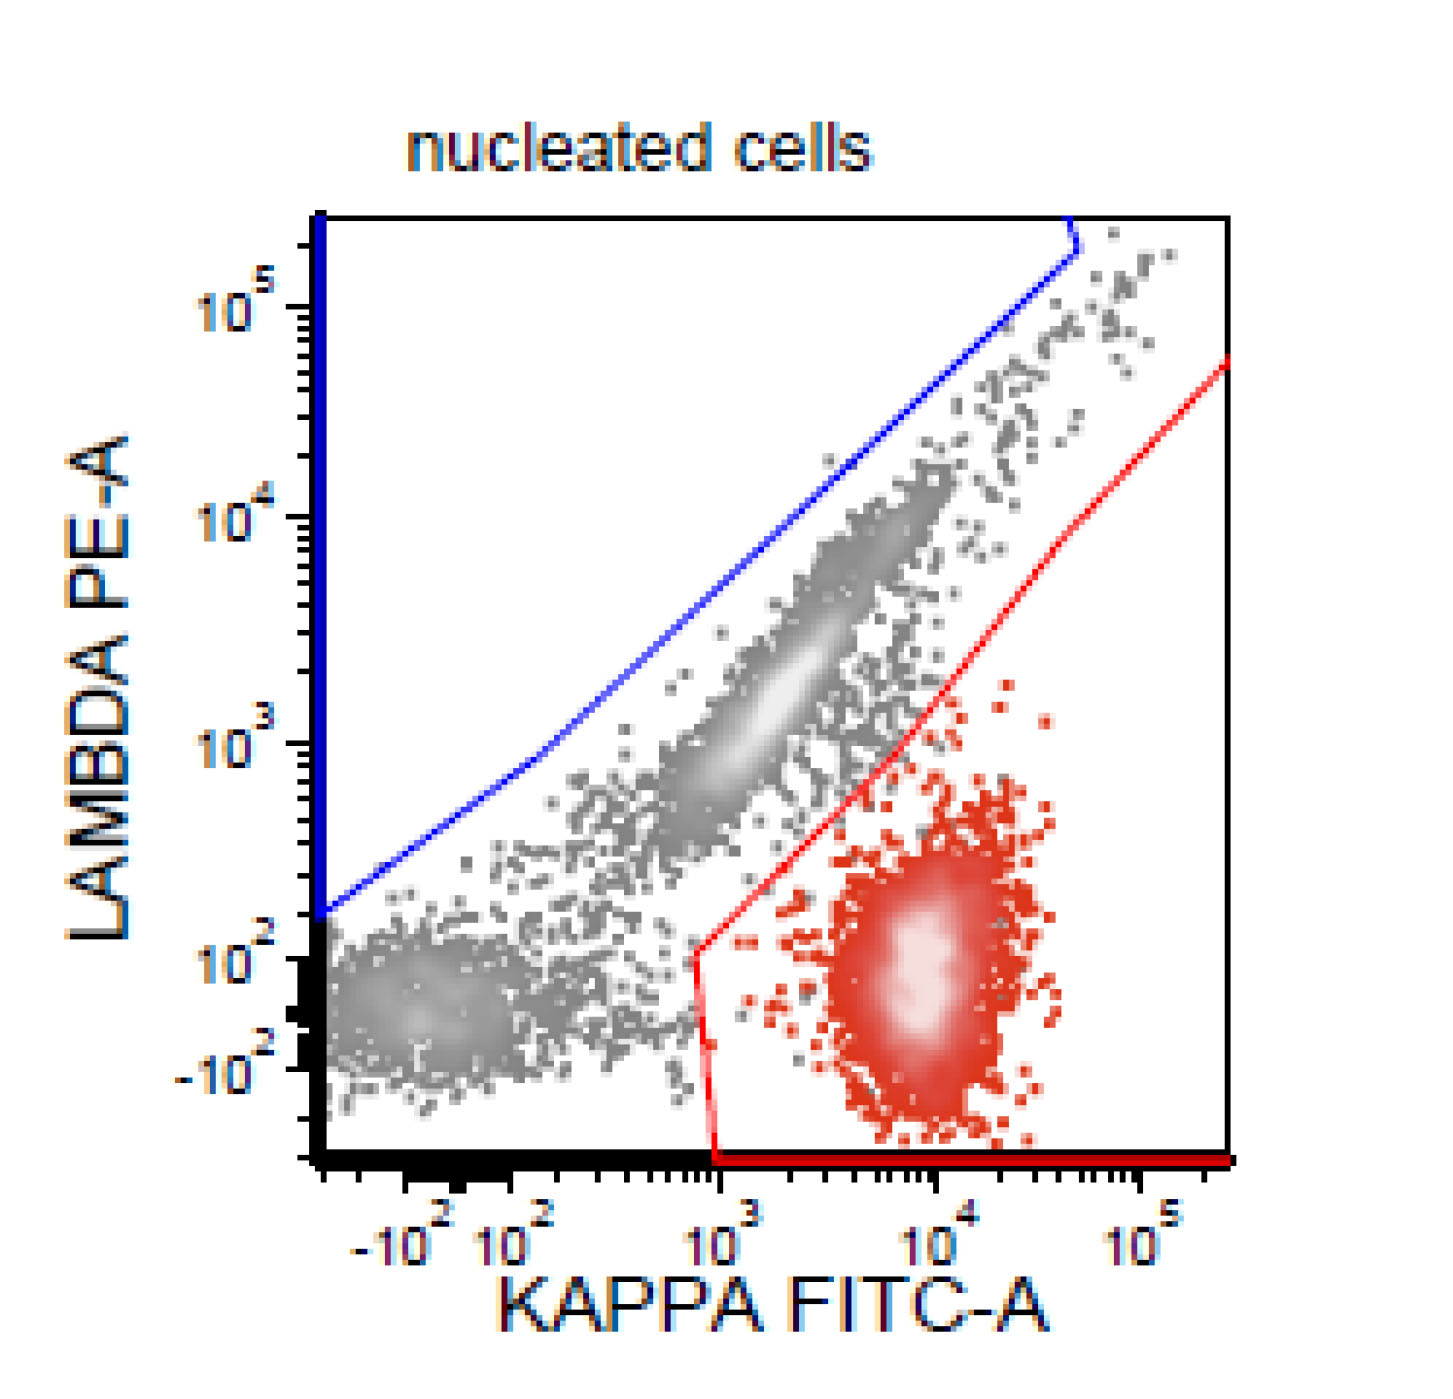

Flow cytometry description

- CD5+, CD19+, CD20+, CD22+, CD79b+, FMC7+

- Monotypic Ig (high level expression of surface light chains)

- CD11c variable, CD43 variable, CD200 variable

- CD3-, CD10-, CD23-

- Rare cases have atypical immunophenotype:

- CD5- or CD10+, CD200+ or CD23+ (dim ~10%)

Flow cytometry images

Flow cytometry immunophenotyping detected a lambda restricted B cell population positive for CD10, CD19, CD20, CD22, CD38, CD79b; while negative for CD5, CD11c, CD30, CD43, CD44, CD200 and kappa light chain.

- This is the concurrent fine needle aspiration flow cytometry of the lymph node in a 70 year old man with lymphadenopathy. Cytology smears show intermediate to large lymphoid cells in a necrotic background. What is the most probable preliminary diagnosis before further work ups on the excised lymph node?

- Mantle cell lymphoma